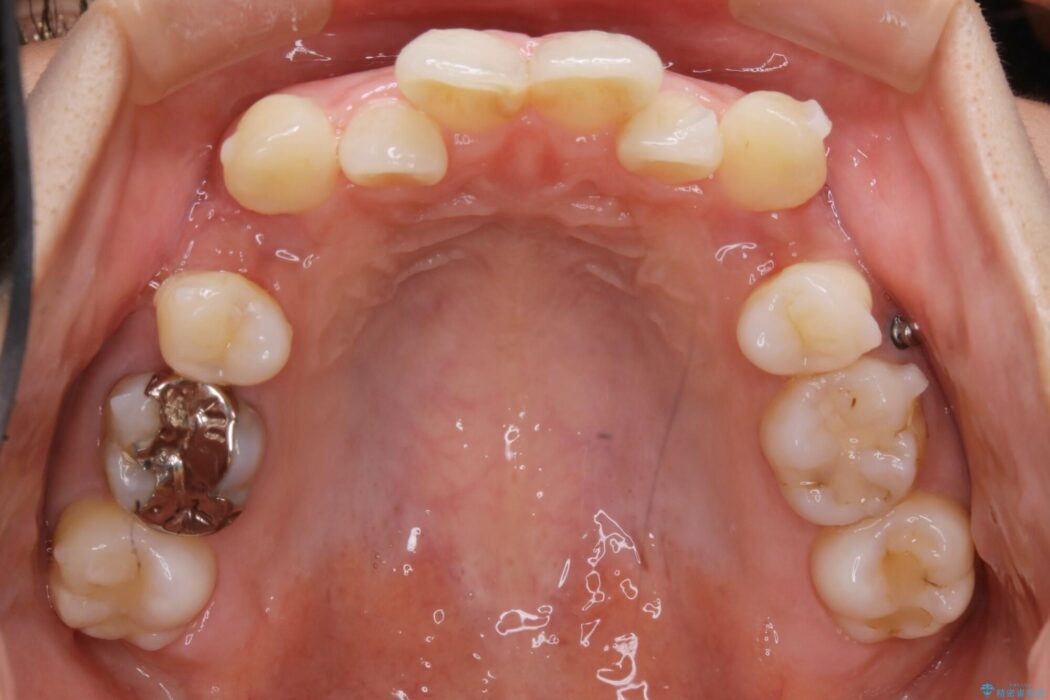

左右の奥歯が前方に寄っていることにより八重歯の発生や重度の叢生に繋がっていました。

ですが詳しく検査をしたところ、左右の奥歯の前後位置に関してはズレが少ない状態でした。

加えて患者様の顎の大きさに対する歯の数が多いことが叢生の原因になっていることから、抜歯した上で歯列を整えるほうが最終的な仕上がりとして良い結果になると判断しました。

まず噛み合わせに問題が少ない奥歯の位置を極力変えないように上下左右4番目の歯を抜歯することで歯列矯正のためのスペースを確保し、空いた隙間で前歯の凹凸をきれいに並べていくこととしました。

また、ご要望がありマイクロインプラント治療もしています。